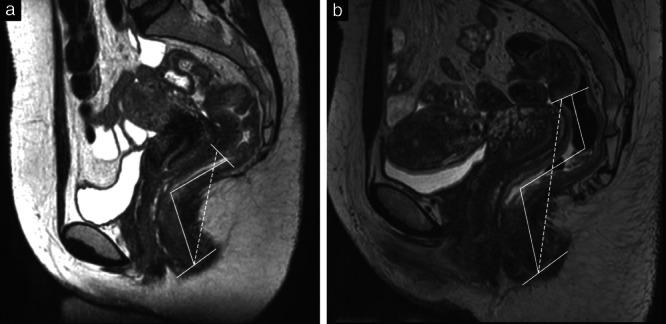

To compare transvaginal sonography (TVS) and magnetic resonance imaging (MRI) with intraoperative measurement (IOM) using a rectal probe in the estimation of the location of rectosigmoid endometriotic lesions, i.e. lesion-to-anal-verge distance (LAVD), and to compare two different MRI techniques for measuring LAVD.

This was a prospective single-center observational study that included women undergoing surgery for symptomatic rectosigmoid endometriosis by discoid (DR) or segmental (SR) resection from December 2018 to December 2019. TVS and MRI were performed presurgically for each participant to evaluate LAVD, and the measurements on imaging were compared with IOM using a rectal probe. Clinically acceptable difference and limits of agreement (LoA) between TVS and MRI compared with IOM were set at ± 20 mm. Two different measuring methods for MRI, MRI and MRI , were proposed and evaluated, as there is currently no guideline to describe deep endometriosis on MRI. Bland-Altman plots and LoA were used to assess agreement of TVS and both MRI methods with IOM. Systematic and proportional biases were assessed using paired t-test and Bland-Altman plots.

Seventy-five women were eligible for inclusion. Twenty-eight women were excluded, leaving 47 women for the analysis. Twenty-three DR and 26 SR procedures were performed, with both procedures performed in two women. The Bland-Altman plots showed that there were no systematic differences between TVS or MRI when compared with IOM for all included participants. MRI systematically underestimated LAVD for lesions located further from the anal verge. TVS, MRI and MRI had LoA outside the preset clinically acceptable difference when compared with IOM. LAVD was within the clinically acceptable difference from IOM of ± 20 mm in 70% (33/47) of women on TVS, 72% (34/47) of women on MRI and 47% (22/47) of women on MRI .